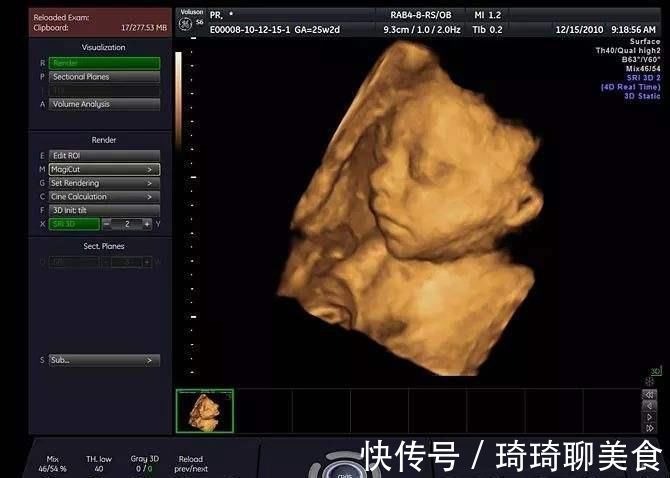

胎儿受到挤压

胎儿在子宫内的时候,空间有限,还受到羊水的压力,鼻子实际上是有些扁平的,就是一种塌鼻子的状态,出生之后,没有这个压力,会逐渐变得舒展,鼻子就会开始呈现他本来的样子,逐渐挺拔,该高就高,该尖就尖。

胎儿本身鼻子大

如果胎儿本身的鼻子非常大,照出来以后自然也不会太小了,可以看一下爸爸妈妈的鼻子,是不是比较大,如果本身也不小的话,就是遗传起作用,完全不用担心了。如果自己的鼻子不大,可能是上面这些原因造成的,不要给自己造成太多困扰。

总之,四维彩超宝宝鼻子偏大也是正常现象,只要胎儿的鼻子结构没有问题,就大可放心,毕竟,做四维彩超主要目的是排除畸形,不是为了给宝宝拍一张修饰好的美颜照片。您说呢?